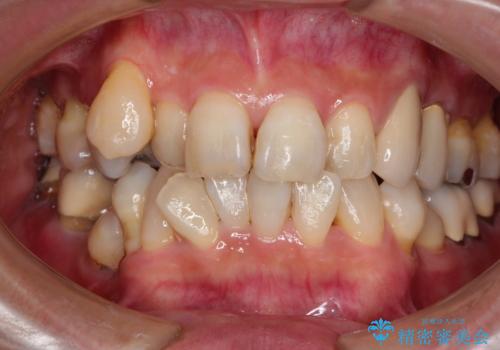

抜歯が必要な左右の奥歯 ブリッジとインプラントによる奥歯の補綴治療